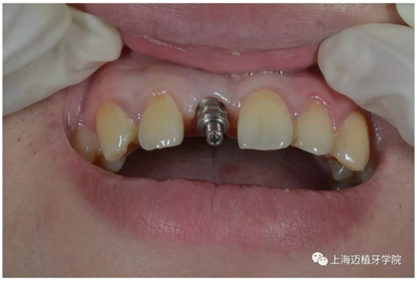

口內(nèi)個(gè)性化基臺(tái):

戴牙 最終修復(fù)效果